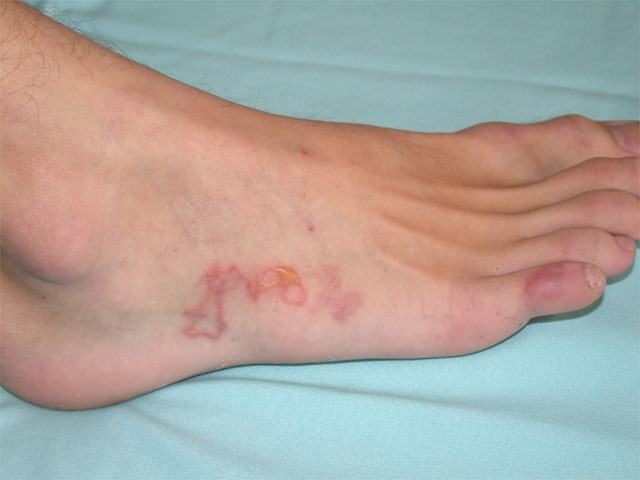

Cutaneous Larva Migrans

Cutaneous larva migrans (CLM) is a creeping cutaneous eruption caused by dog (Ancylostoma caninum) or cat (A braziliense) hookworm larvae. Most infections are acquired from walking barefoot on contaminated sand (beaches) or soil. Humans are incidental hosts, and larvae are typically unable to penetrate the dermal basement membrane. As a result, cutaneous infection without deeper penetration is the norm.

Most infections occur in the lower extremities (70%), and symptoms usually start with a pruritic, erythematous papule at the site of larvae penetration (which may go unnoticed). Within a few days, patients develop symptoms related to larvae migration: intensely pruritic, serpiginous, reddish-brown cutaneous tracks. Although most cases resolve spontaneously after a few weeks, antihelmintics (eg, ivermectin) are usually given to aid clearance.